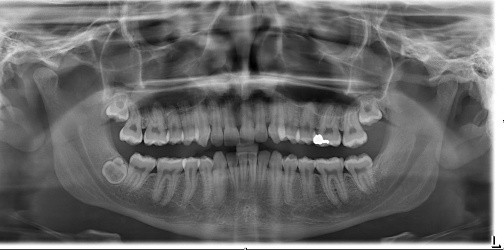

12. (Select ONE OR MORE correct answers.)

Tooth 4.8 is planned for extraction. Which radiographic findings suggest an increase in the degree of difficulty of the extraction?

13. (Select ONE OR MORE correct answers.)

Tooth 2.8 is planned for extraction. Which radiographic findings suggest an increase in the degree of difficulty of the extraction?

16. (Select ONE OR MORE correct answers.)

Tooth 1.8 is planned for surgical extraction. Which radiographic findings suggest an increase in the degree of difficulty of the extraction?

18. Select ONE OR MORE correct answers.)

Tooth 2.8 is planned for surgical extraction. Which radiographic findings suggest an increase in the degree of difficulty of the extraction?

25. (Select ONE OR MORE correct answers.)